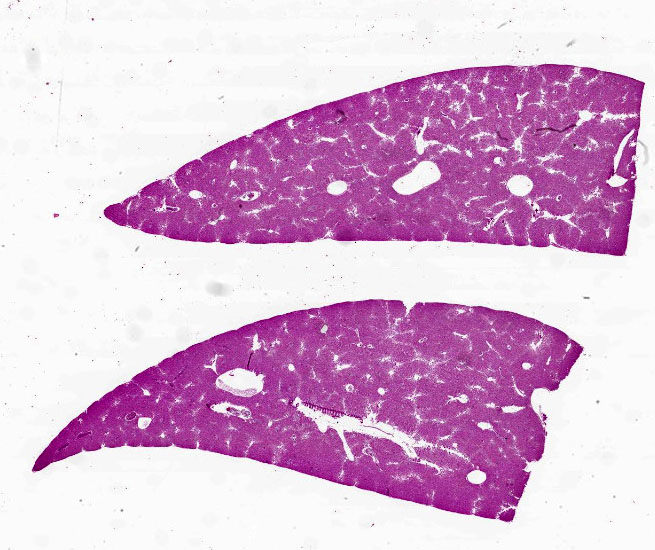

Microscopic Description:

Liver: Diffusely filling portal veins and expanding sinusoids is a neoplastic population composed of round cells with distinct cell borders, small amount of eosinophilic, granular cytoplasm, round to occasional reniform nucleus, clumped chromatin and indistinct nucleolus. Mitotic rate is <1 per hpf.

Diffusely centrilobular hepatocytes are lost, degenerating or necrotic. Diffusely there is lobular atrophy and sinusoids are expanded by previously described neoplastic cells admixed with eosinophilic cellular debris. Multifocally centrilobular kupffer cells and/or hepatocytes contain hemosiderin pigment. Multifocally within portal regions there is an increase in small bile duct profiles (ductular reaction). Rarely, bile duct epithelial cells are degenerative, necrotic or undergoing regeneration.

Contributor's Morphologic Diagnoses:

Liver: Leukemia, large granular lymphocytic

Histological findings, in general, include diffuse infiltration of the splenic red pulp sinusoids of variable density, infiltration of the hepatic sinusoids with variable centrilobular hepatocellular degeneration, and necrosis and atrophy of hepatic cords and infiltration of the alveolar septa of the lungs.7 Other tissues affected include lymph nodes, adrenal gland, kidney, and bone marrow.